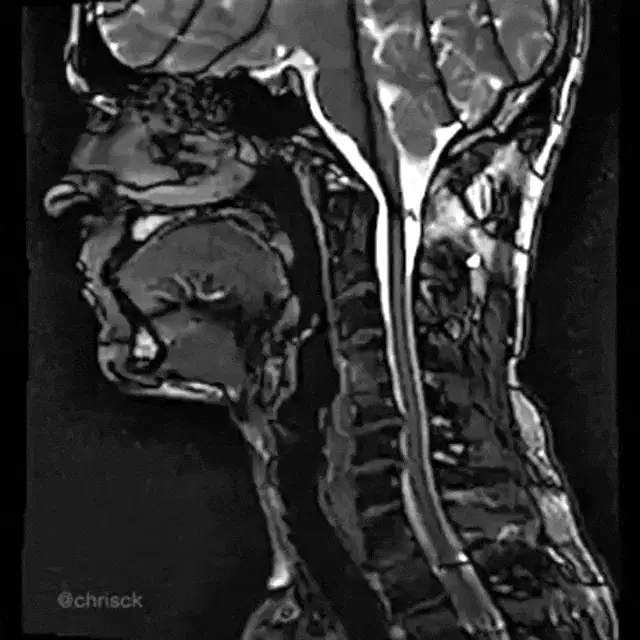

Mandibular Retraction